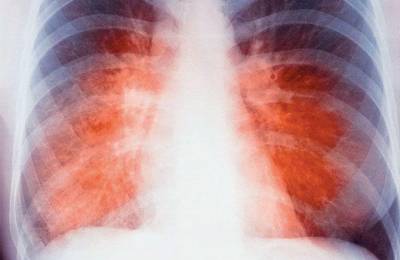

Отмечается комплекс функциональных нарушений со стороны некоторых органов под масками других заболеваний. Заболевание может напоминать ревмокардит: появляются боли в сердце, сердцебиение, изменения на ЭКГ, боли в суставах. Могут быть симптомы поражения бронхолегочного аппарата: кашель, жесткое дыхание, сухие хрипы, усиление прикорневого рисунка на рентгенограмме – маска бронхита. Симптомы поражения желудочно-кишечного тракта – ухудшение аппетита, похудание, диспепсические проявления. Такие функциональные расстройства неспецифичны и связаны с особенностями реактивности организма детей, заключающиеся в превалировании общих нервных и сосудистых реакций над местными изменениями.

При обследовании ребенка следует обратить внимание на микрополиаденит. Лимфатические узлы мягкоэластической консистенции, безболезненные, подвижные, пальпируются 6-8 групп (шейные, подмышечные, затылочные, паховые и др.). В гемограмме повышена СОЭ, умеренный лейкоцитоз, палочкоядерный сдвиг влево, лимфопения, моноцитоз, эозинофилия. В моче могут наблюдаться изменения в виде небольшого количества белка, гематурии, лейкоцитоурии. На рентгенограмме очагов в легких и увеличенных внутригрудных лимфатических узлов не обнаруживают.

- Рентгенография. Не выявляет очагов специфического (гранулематозного) воспаления легких в виде теней. Возможны усиление легочного рисунка и образование кальцинатов (солевых отложений).

- Ежегодное флюорографическое исследование показывает неспецифические изменения в лёгких и окружающих тканях.

Для постановки диагноза делают общий анализ крови, рентгенографический снимок в прямой и боковых проекциях, проводят исследование мокроты с определением специфических клеток.

- Дети склонны к бронхоадениту (увеличение группы лимфоузлов в области рядом с бронхами), поэтому на рентгенограмме чаще выявляется воспаление в этой области.

Особенность данного патологического процесса — отсутствие изменений в легких по данным рентгенологических исследований.

| Рентген, флюорография | Для картины туберкулезной интоксикации характерно отсутствие специфического поражения ткани легкого. |

Туберкулезная интоксикация не диагностируется рентгенологически, для этого делается обзорная рентгенограмма или срединная томограмма.